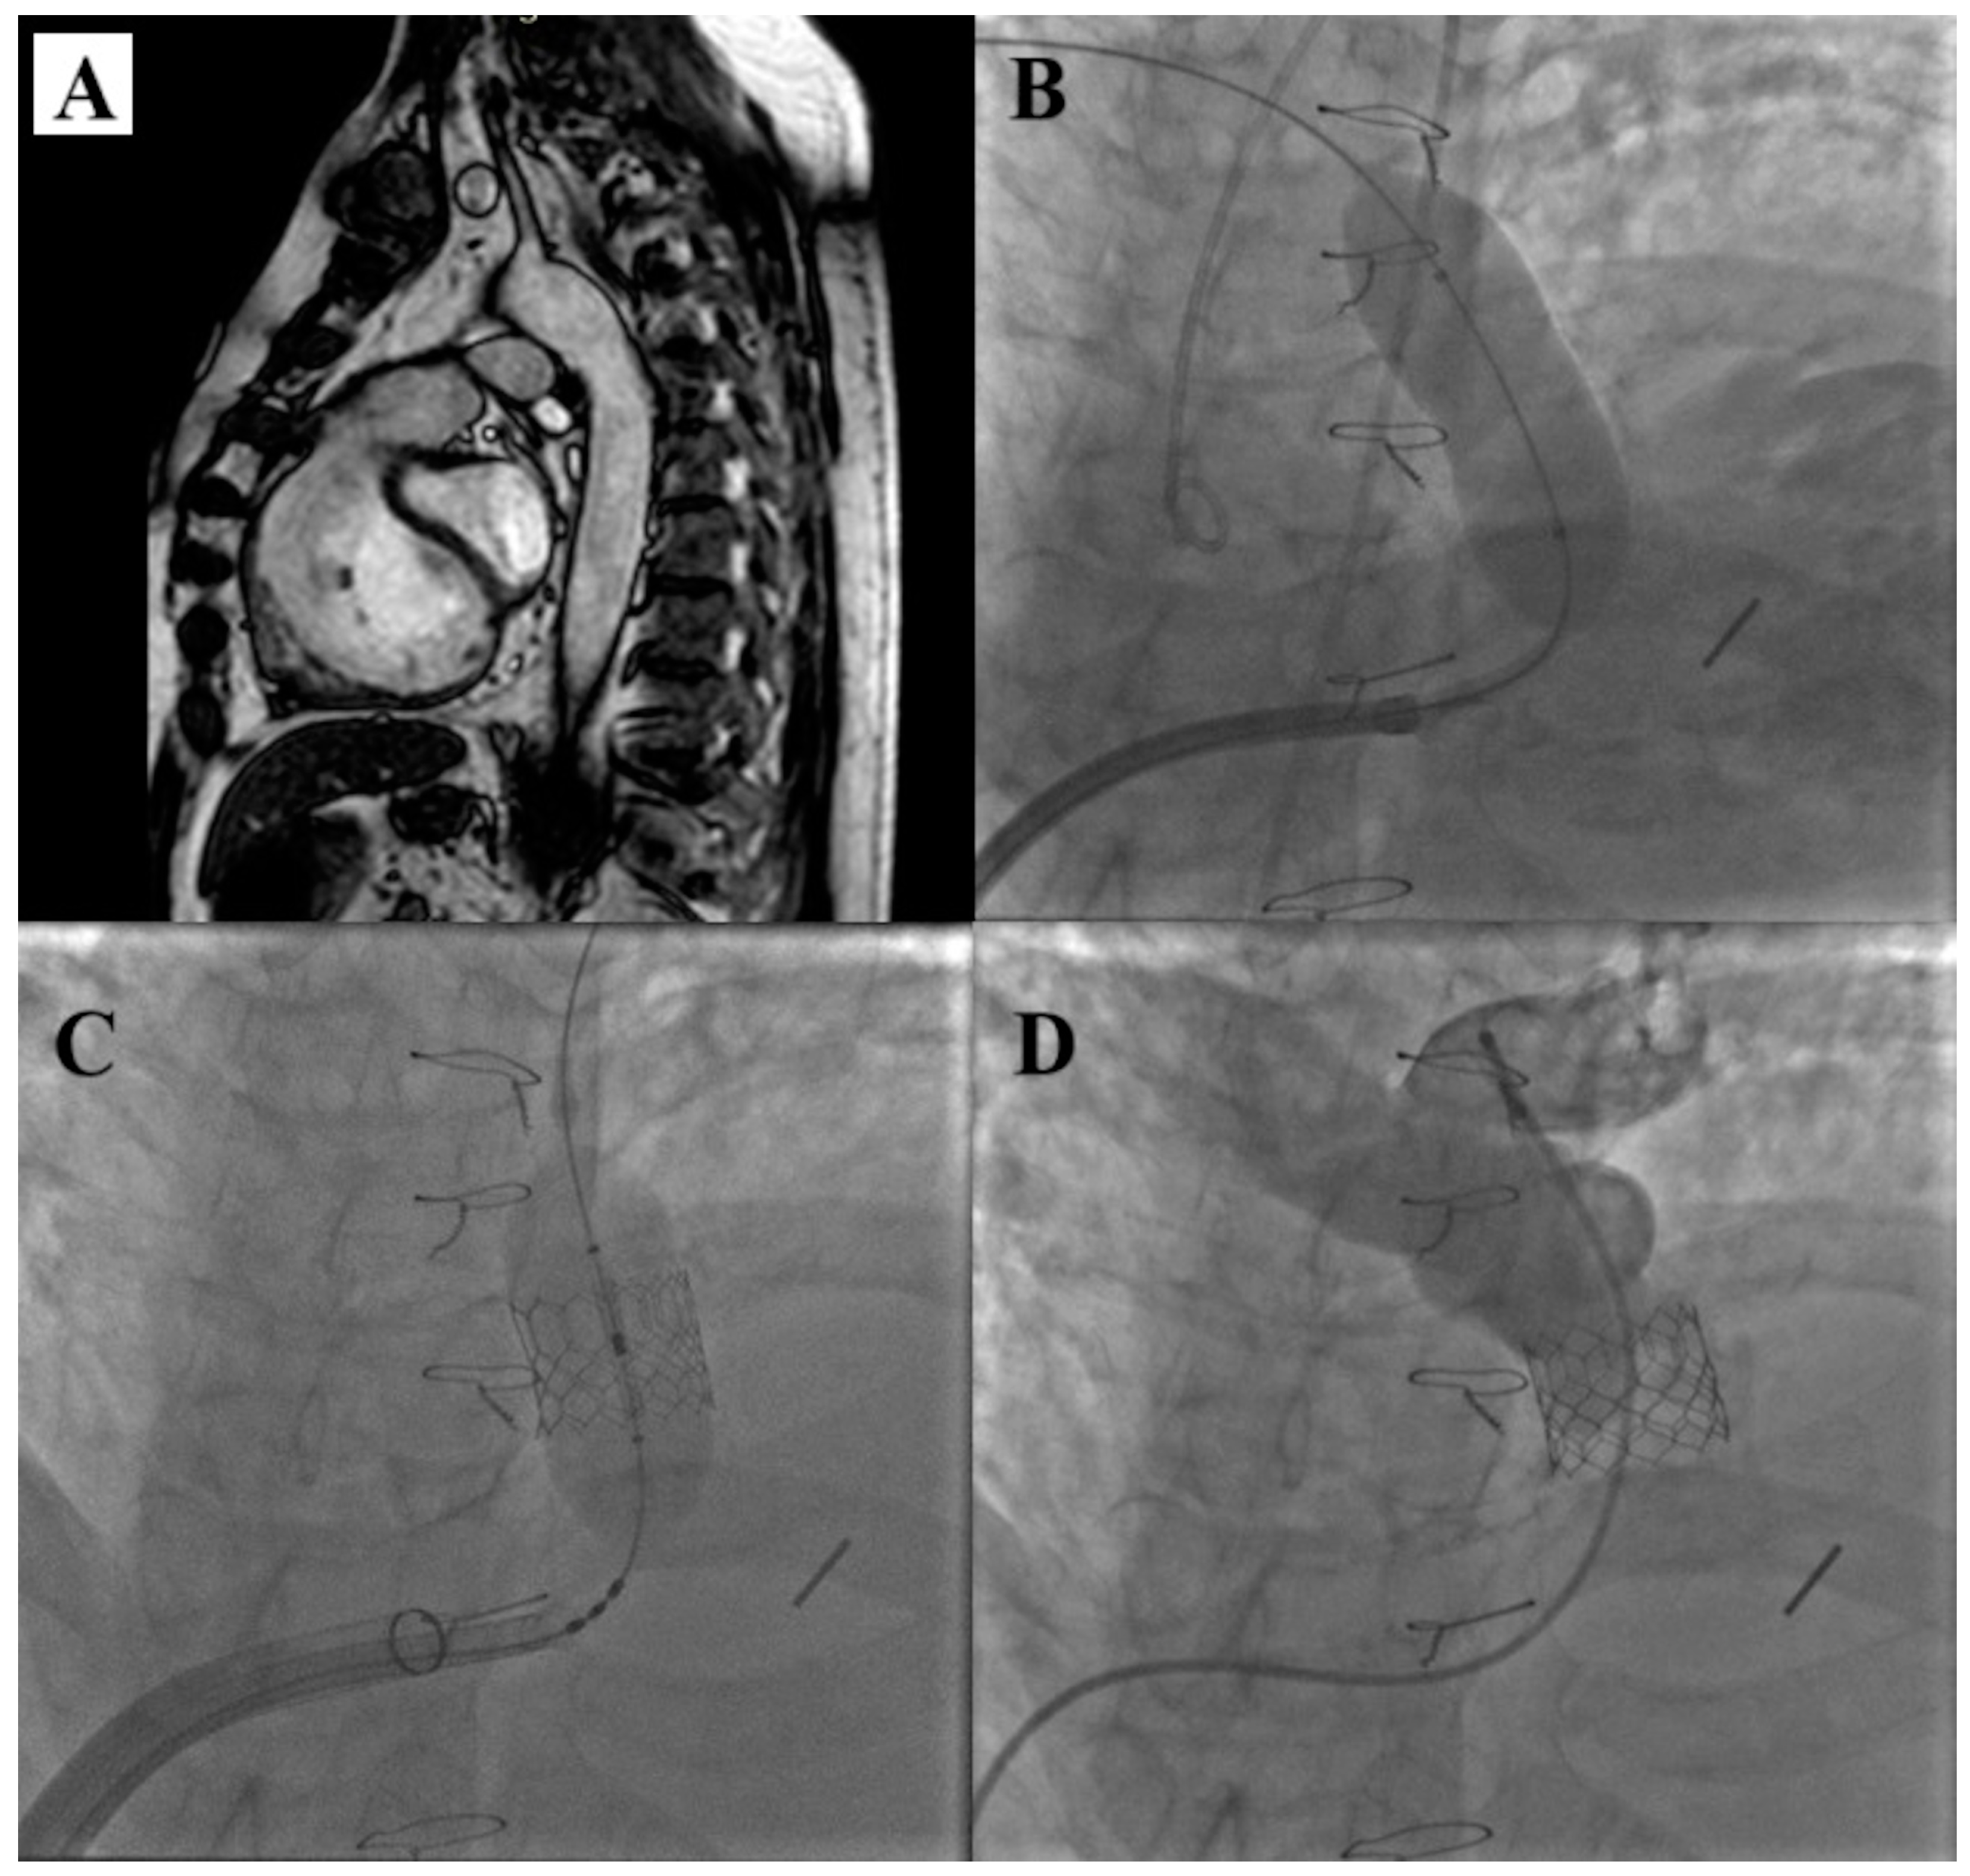

7. Alterra Adaptive Prestent

- Zahn, E.M.; Chang, J.C.; Armer, D.; Garg, R. First human implant of the Alterra Adaptive Prestent TM: A new self-expanding device designed to remodel the right ventricular outflow tract. Catheter. Cardiovasc. Interv. 2018, 91, 1125–1129. [Google Scholar] [CrossRef]

- Dimas, V.V.; Babaliaros, V.; Kim, D.; Lim, D.S.; Morgan, G.; Jones, T.K.; Armstrong, A.K.; Berman, D.; Aboulhosn, J.; Mahadevan, V.S.; et al. Multicenter Pivotal Study of the Alterra Adaptive Prestent for the Treatment of Pulmonary Regurgitation. JACC Cardiovasc. Interv. 2024, 17, 2287–2297. [Google Scholar] [CrossRef]